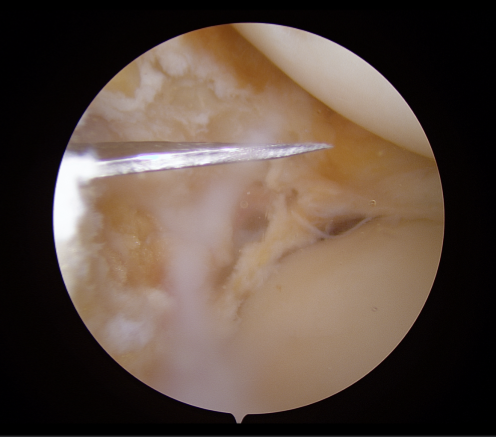

▶수술 전_관절내시경 사진 01

영상검사를 통해 확인한 소견은 비교적 명확했습니다.

- - 외측 대퇴골(LFC)에 발생한 거대 골연골박리(OCD, Osteochondral Defect)

- - 외측 반월상연골(Lateral Meniscus) 파열

- - 오른쪽 무릎의 외반 변형(Valgus knee)

특히 문제였던 것은 OCD 병변의 크기가 ‘Huge’ 수준이었다는 점입니다.